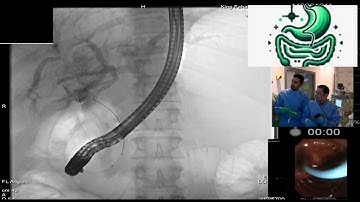

Cholangioscopy Micro Tech EyeMax. Difficult CBD stones